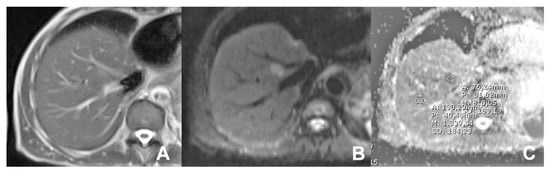

2. Liver